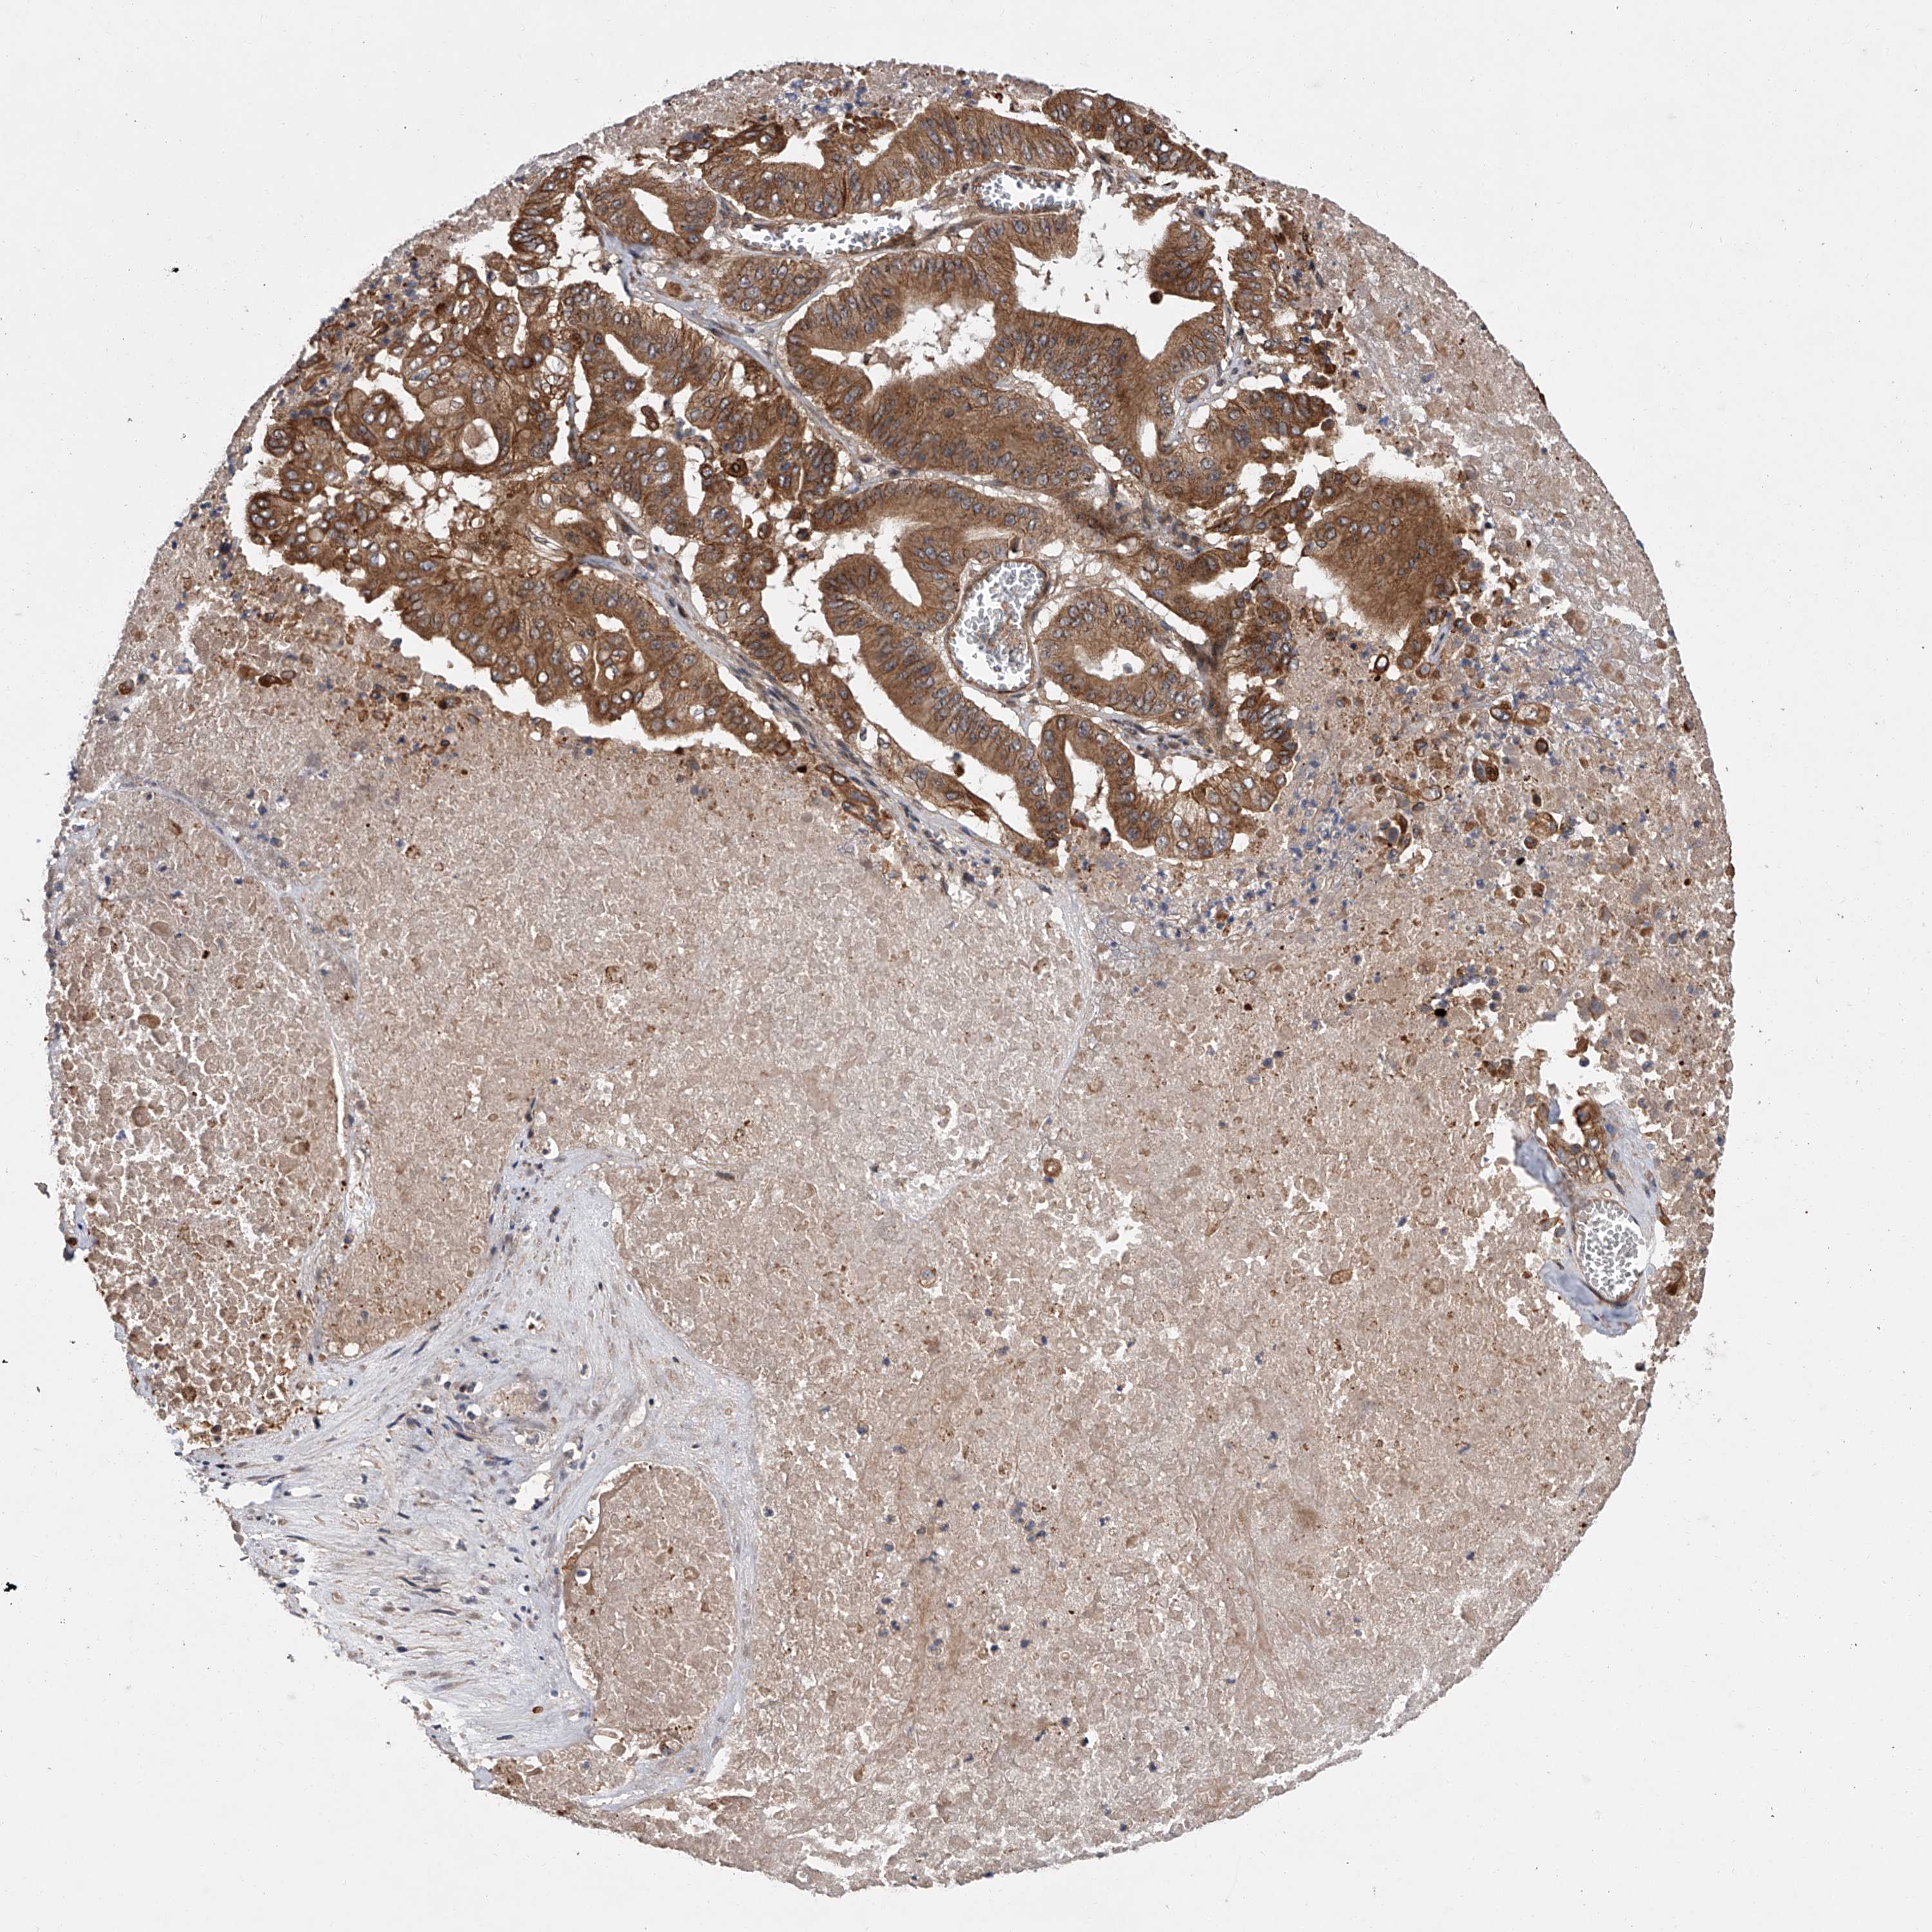

PANCREATIC CANCER - Protein expressioni

A mouse-over function shows sample information and annotation data. Click on an image to view it in a full screen mode. Samples can be filtered based on level of antibody staining by selecting one or several of the following categories: high, medium, low and not detected. The assay and annotation is described here.

Note that samples used for immunohistochemistry by the Human Protein Atlas do not correspond to samples in the TCGA dataset.

Antibody stainingi

Antibody staining in the annotated cell types in the current human tissue is reported as not detected, low, medium, or high, based on conventional immunohistochemistry profiling in selected tissues. This score is based on the combination of the staining intensity and fraction of stained cells.

Each image is clickable and will lead to virtual microscopy that enables deeper exploration of all samples and also displays staining intensity scores, fraction scores and subcellular localization as well as patient and tissue information for each sample.

Antibody HPA029286

Antibody HPA029289

Adenocarcinoma, NOS